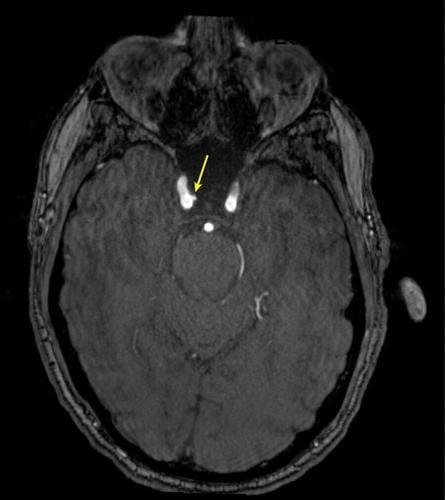

Representative axial time-of-flight MR angiography image in a 35-year-old male participant shows a medially projecting intracranial aneurysm (arrow) originating from the right cavernous segment of the internal carotid artery. (RSNA via SWNS)